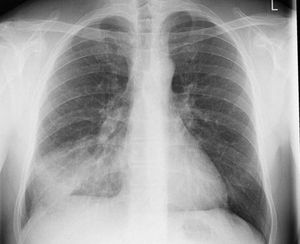

Right costophrenic angle is clear.. no fluid so not pleural effusion...Shadow indicating pnumonitis....associated rib fracture...oblique view to rule out fracture rib..

Pleural effusion bcz of haziness and obliteration of demarcation line(on rt side)